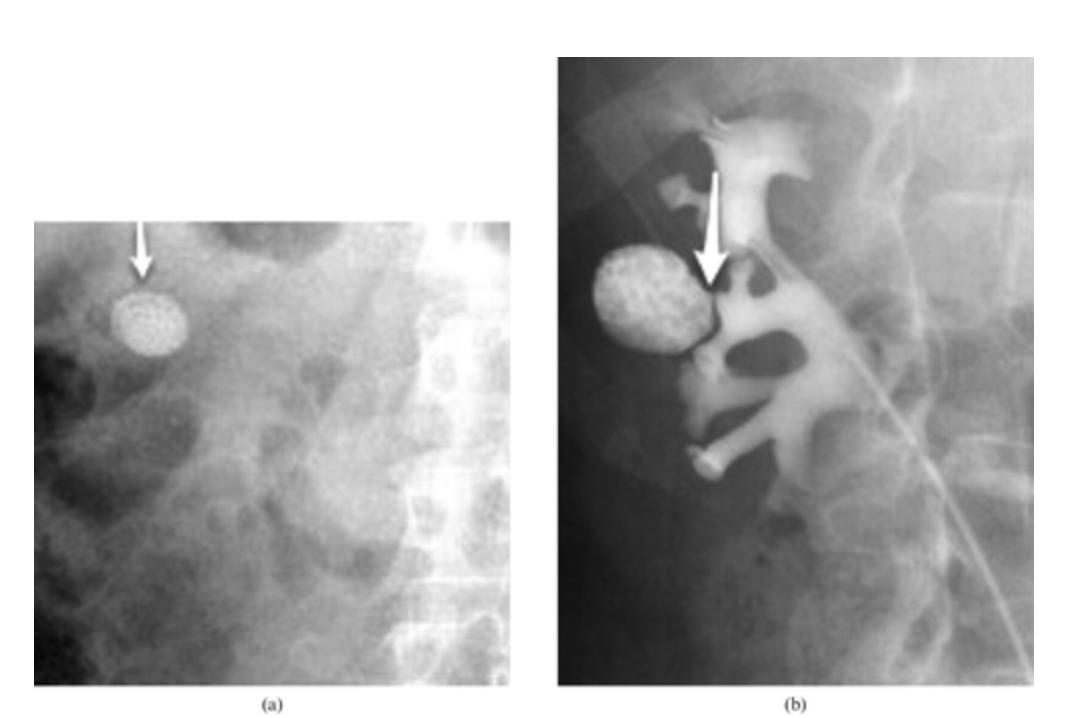

What is this?

What are the types?

Symptoms?

PyeloCalyceal Diverticulum

A 47-year-old male with right flank pain. (a) A magnified view from a control film of an intravenous urogram (IVU) demonstrates a 2 cm opacity in the right upper quadrant (arrow). This image clearly shows that the opacity is made up of multiple tiny calculi rather than a single large calculus, which should raise the suspicion that they lie within a calyceal diverticulum. (b) An oblique radiograph from a retrograde pyelogram study elegantly depicts the short, narrow infundibulum of a calyceal diverticulum arising from a mid-pole calyx (arrow).

https://www.birpublications.org/doi/10.1259/bjr/22591022